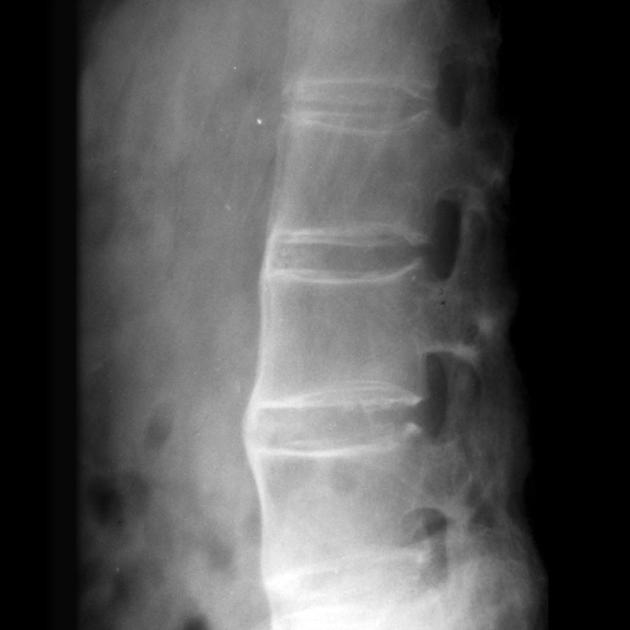

强直性脊柱炎 付费文章

强直性脊柱炎的常规医疗治疗方案